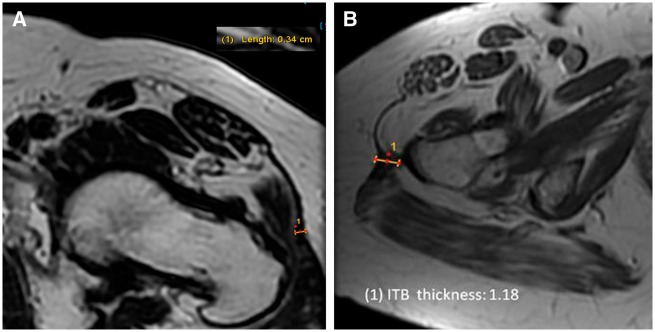

ITB diameter thickness was measured in the axial plane of MRIs. The ITB measurement location was considered as the region of greatest thickness between the most proximal images of the greater trochanter to the most proximal sequence showing the lesser trochanter (Fig. 1). The MRI’s for both subject groups were examined and repeat measurements taken for inter/intra class correlation (ICC) analysis. Two examiners independently assessed ITB thickness measurements for both subject groups. The averages of the two sets were used for statistical analysis. An ICC coefficient analysis was performed for the collected values to determine the validity of the measurements. The images were then reviewed to document the location of the greatest thickness as anterior, lateral or posterior.

Fig. 1.

ITB measurement. The ITB measurement location was considered as the region of greatest thickness between the most proximal images of the greater trochanter to the most proximal sequence showing the lesser trochanter. (A) Asymptomatic subject measurement. ITB thickness was measured to be 0.34 cm. (B) Increased ITB thickness measurement. ITB thickness was measured to be 1.18 cm.